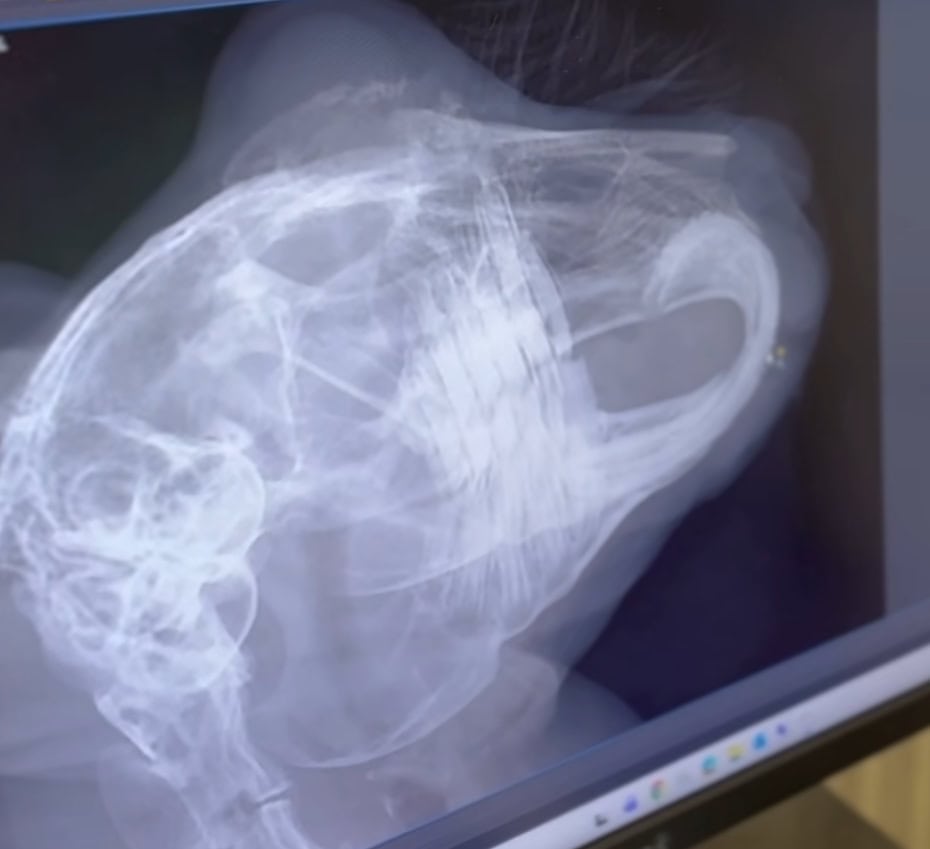

Abgabekaninchen Chili hat ein großes Problem: Seine unteren Schneidezähne sind so hemmungslos gewachsen, dass sie in seinem Mäulchen in einem Bogen von unten nach oben in seinen Oberkiefer eingedrungen sind.

Er wollte nichts mehr fressen – kein Wunder, es passte nicht an den Zähnen vorbei. Außerdem muss Chili ganz große Schmerzen gehabt haben. Seine Zähne waren schon so lang gewachsen, dass sie beinah durch seinen Oberkiefer aus seinem Gaumen wieder in die Maulhöhle ausgetreten sind.